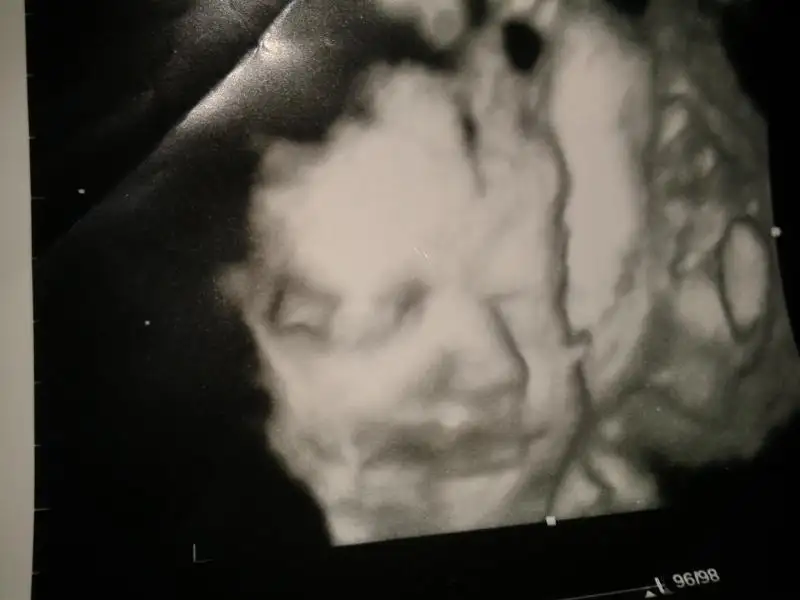

kızımın resmini koyuyorum sizlere..12 ekimde gittik..30+3tük...usgye göre 31+5 çıktık...1894 gr kızmız...gülüp ddurdu bize teyzlerii